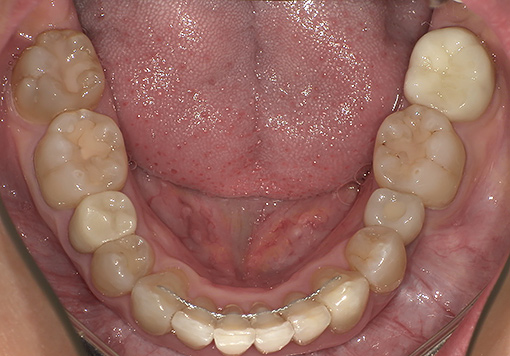

Case 04

before

after

- 主訴:前歯のガタつき・上下の歯並びの不均一を改善したい。

根管治療途中の歯を治したい - 治療内容:マウスピース型矯正装置(SureSmile)による全顎矯正。

下顎1本インプラント埋入 - 治療期間:約36ヶ月

- 診断結果:

・上下顎に叢生を認め、特に上顎前歯部の位置不良が強い状態。

・噛み合わせのズレがあり、審美性・機能性の改善が必要と判断。

・抜歯を伴わないマウスピース矯正での改善が可能と診断。

歯根破折 - 治療後経過:

・前歯部の配列が整い、正中・噛み合わせが改善。経過も良好。 - 治療費用:マウスピース矯正(SureSmile):88万円税込

インプラント45万円税込

※症例により費用は前後します。